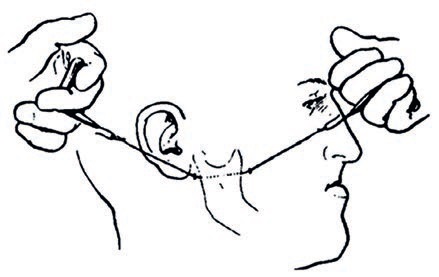

Wprowadzenie: Planowanie leczenia protetycznego

wymaga wykonania przez pacjenta diagnostycznego zdjęcia

panoramicznego. Wykrycie zębów nieprawidłowo leczonych

endodontycznie, nawet asymptomatycznych, zębów ze stanem zapalnym

tkanek okołowierzchołkowych, kanałów wypełnionych z pozostawionymi

złamanymi narzędziami, zobowiązuje lekarza do przeprowadzenia

ponownego leczenia kanałowego. Cel pracy: W pracy

opisano własny przypadek pacjentki ze złamaną igłą LENTULO w kanale

korzeniowym oraz przedstawiono sposób jej usunięcia.

Podsumowanie: Usuwanie złamanego narzędzia z

kanału korzeniowego jest skomplikowanym i trudnym zabiegiem,

wymagającym umiejętności, zdolności manualnych, znajomości anatomii

systemu kanałowego oraz specjalistycznego sprzętu i urządzeń.